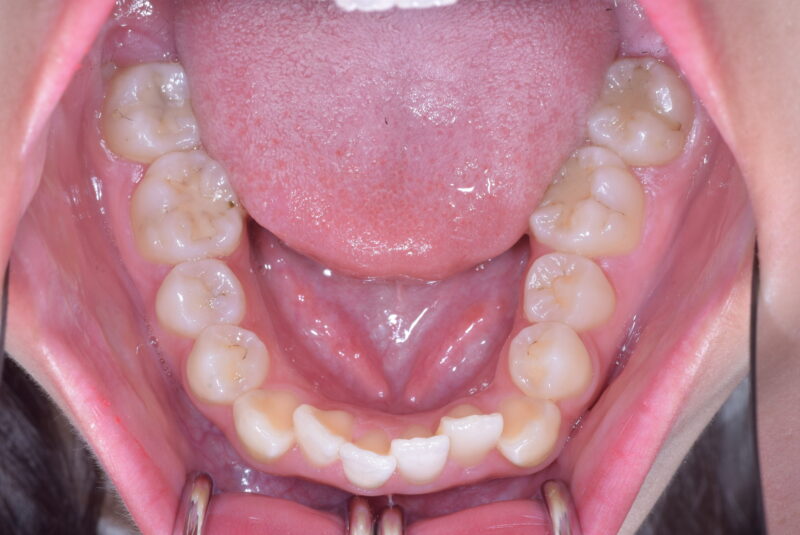

症例27 重度叢生症例

・治療前

・治療中

・治療後

①主訴 歯ならびが悪い

②診断名 前歯部叢生 Angle Cl. I

③年齢 20代女性

④治療に用いた主な装置 上顎:表側の装置 下顎:表側の装置

⑤抜歯部位 上顎:左右第一小臼歯 下顎:左右第一小臼歯

⑥治療期間 1年5か月

⑦治療費 850,000円

⑧リスク副作用 痛み・治療後の後戻り・歯根吸収・歯髄壊死・歯肉退縮などが一般的なリスクと副作用です。